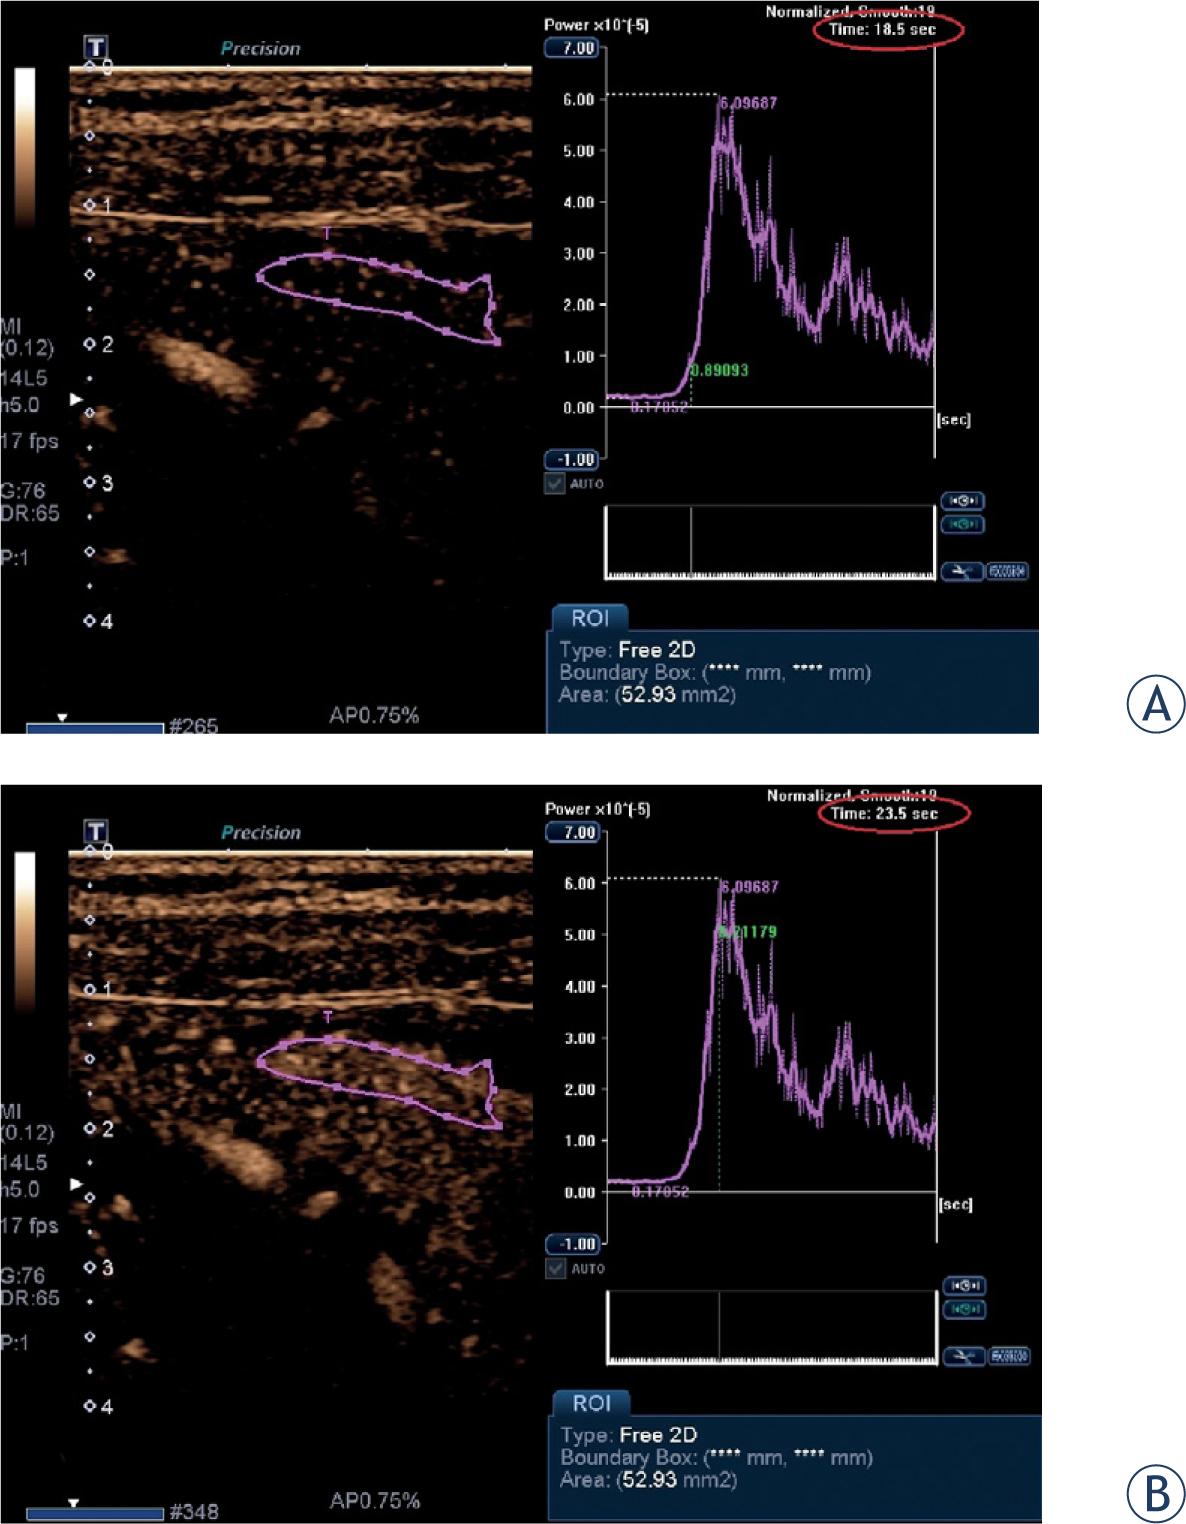

Contrast-enhanced ultrasound: the region of interest (ROI) is determined (A) when the contrast medium first appears in the affected bowel wall corresponding to starting point at time-intensity curve, (B) when the maximum enhancement was seen corresponding to peak at time-intensity curve. The calculated time-to-peak is 5 seconds (18.5 sec to 23.5).